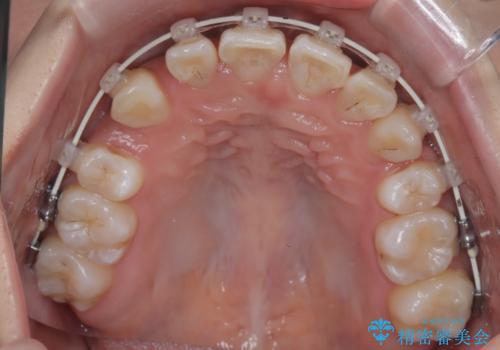

今回の矯正治療では、まず計画通り上下左右の小臼歯4本を抜歯し、八重歯や正中のズレを解消するための十分なスペースを確保しました。装置には、目立ちにくい白いブラケットとワイヤーを使用した審美ワイヤー矯正を採用。

八重歯: 突出していた八重歯を歯列内に誘導し、デコボコを解消しました。

正中のズレ: 歯を左右対称に移動させることで、上下の歯の中心線を正確に合わせ、顔全体のバランスも改善しました。

治療の結果、長年気にされていた八重歯と正中のズレが解消し、機能的にも整った理想的な歯並びを獲得。目立たない装置で治療を完遂し、自信を持って笑える美しい笑顔を手に入れていただけました。